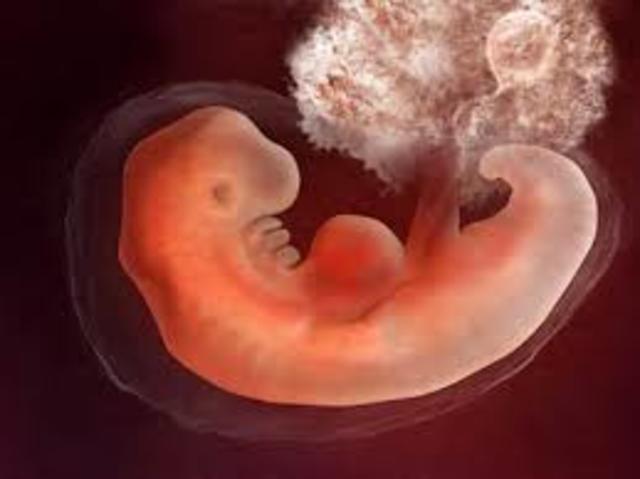

• 2nd Month

2nd Month

6 weeks:

1. 5/8 inches long.

2. Eyelids form.

3. All organs developed.

8 weeks:

1. Bones and muscles developing.

2. Leg buds start to grow.

3. Arm buds start to grow.